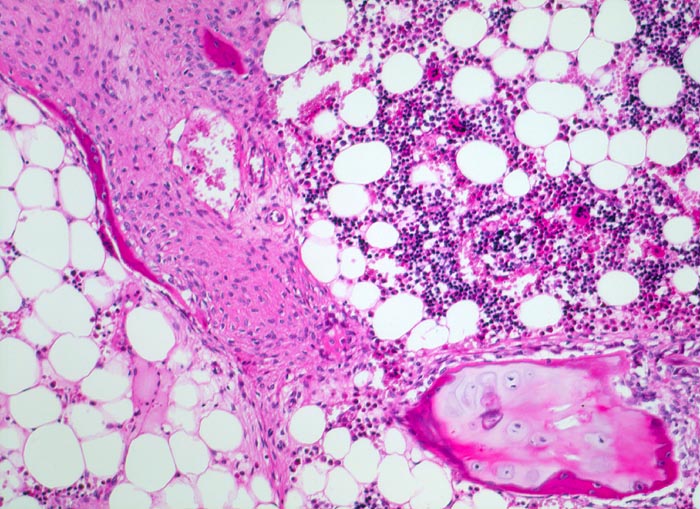

Histologisch charakteristisch ist eine mangelhafte oder fehlende Bildung der primären und sekundären Spongiosa mit multiplen Mikrofrakturen (bei normalen Knorpelzonen) und eine hochgradige Verminderung der desmalen Knochenbildung trotz ausreichend vorhandener oder sogar vermehrt nachweisbarer Osteoblasten. Die einzelnen Kittlinien liegen auffallend nah beieinander. Sekundär kann sich aufgrund der Mikrofrakturen eine reaktive Fibrose und (besonders bei der Osteogenesis imperfecta tarda) eine überschiessende Kallusbildung entwickeln.

• Alte Rippenfraktur mit dislozierten Frakturenden. Sekundäre Frakturheilung mit Ausbildung eines fibroossären Frakturkallus.

• Extrem dünne Corticalis.

• Spongiosa ausserhalb der Fraktur mit ausgeprägter Osteopenie.

• Die Spongiosabälkchen sind stark verdünnt. Die Osteozyten innerhalb der Spongiosabälkchen sind eng zusammengerückt und die einzelnen Knochenlamellen sind ebenfalls verdünnt.

• Alterskorreliert normozelluläres Knochenmark.